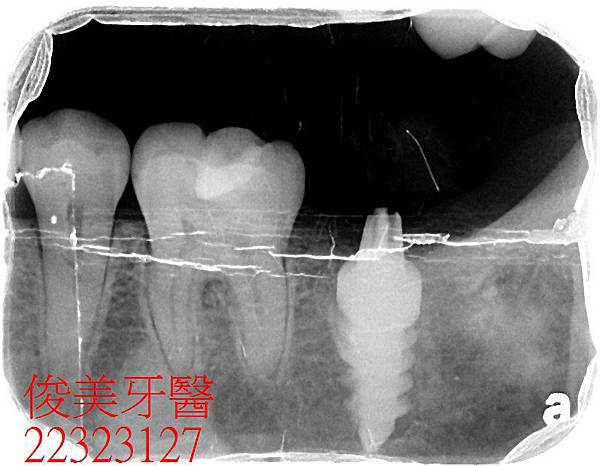

植入人工牙根.......

待骨整合,3個月後~~~~

裝牙齒囉!!患者非常高興,除了解除牙痛的困擾,也在重建過程中,舒適少痛。